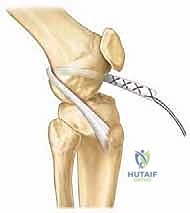

شكل 4: تحديد مسار النفق العظمي بدقة متناهية تحت توجيه الأشعة لضمان بقائه بعيداً عن صفيحة النمو الحساسة.

- إعداد مسار الرباط: بناءً على التقنية المختارة (حفاظاً على صفائح النمو)، يتم تحديد مسار الرباط الجديد بدقة باستخدام أجهزة تصوير إشعاعي داخل غرفة العمليات (Fluoroscopy).

شكل 8: استخدام الأشعة السينية (Fluoroscopy) أثناء الجراحة (Intraoperative) لتأكيد الموقع الدقيق للأنفاق العظمية وأدوات التثبيت والتأكد من عدم مساسها بصفائح النمو.